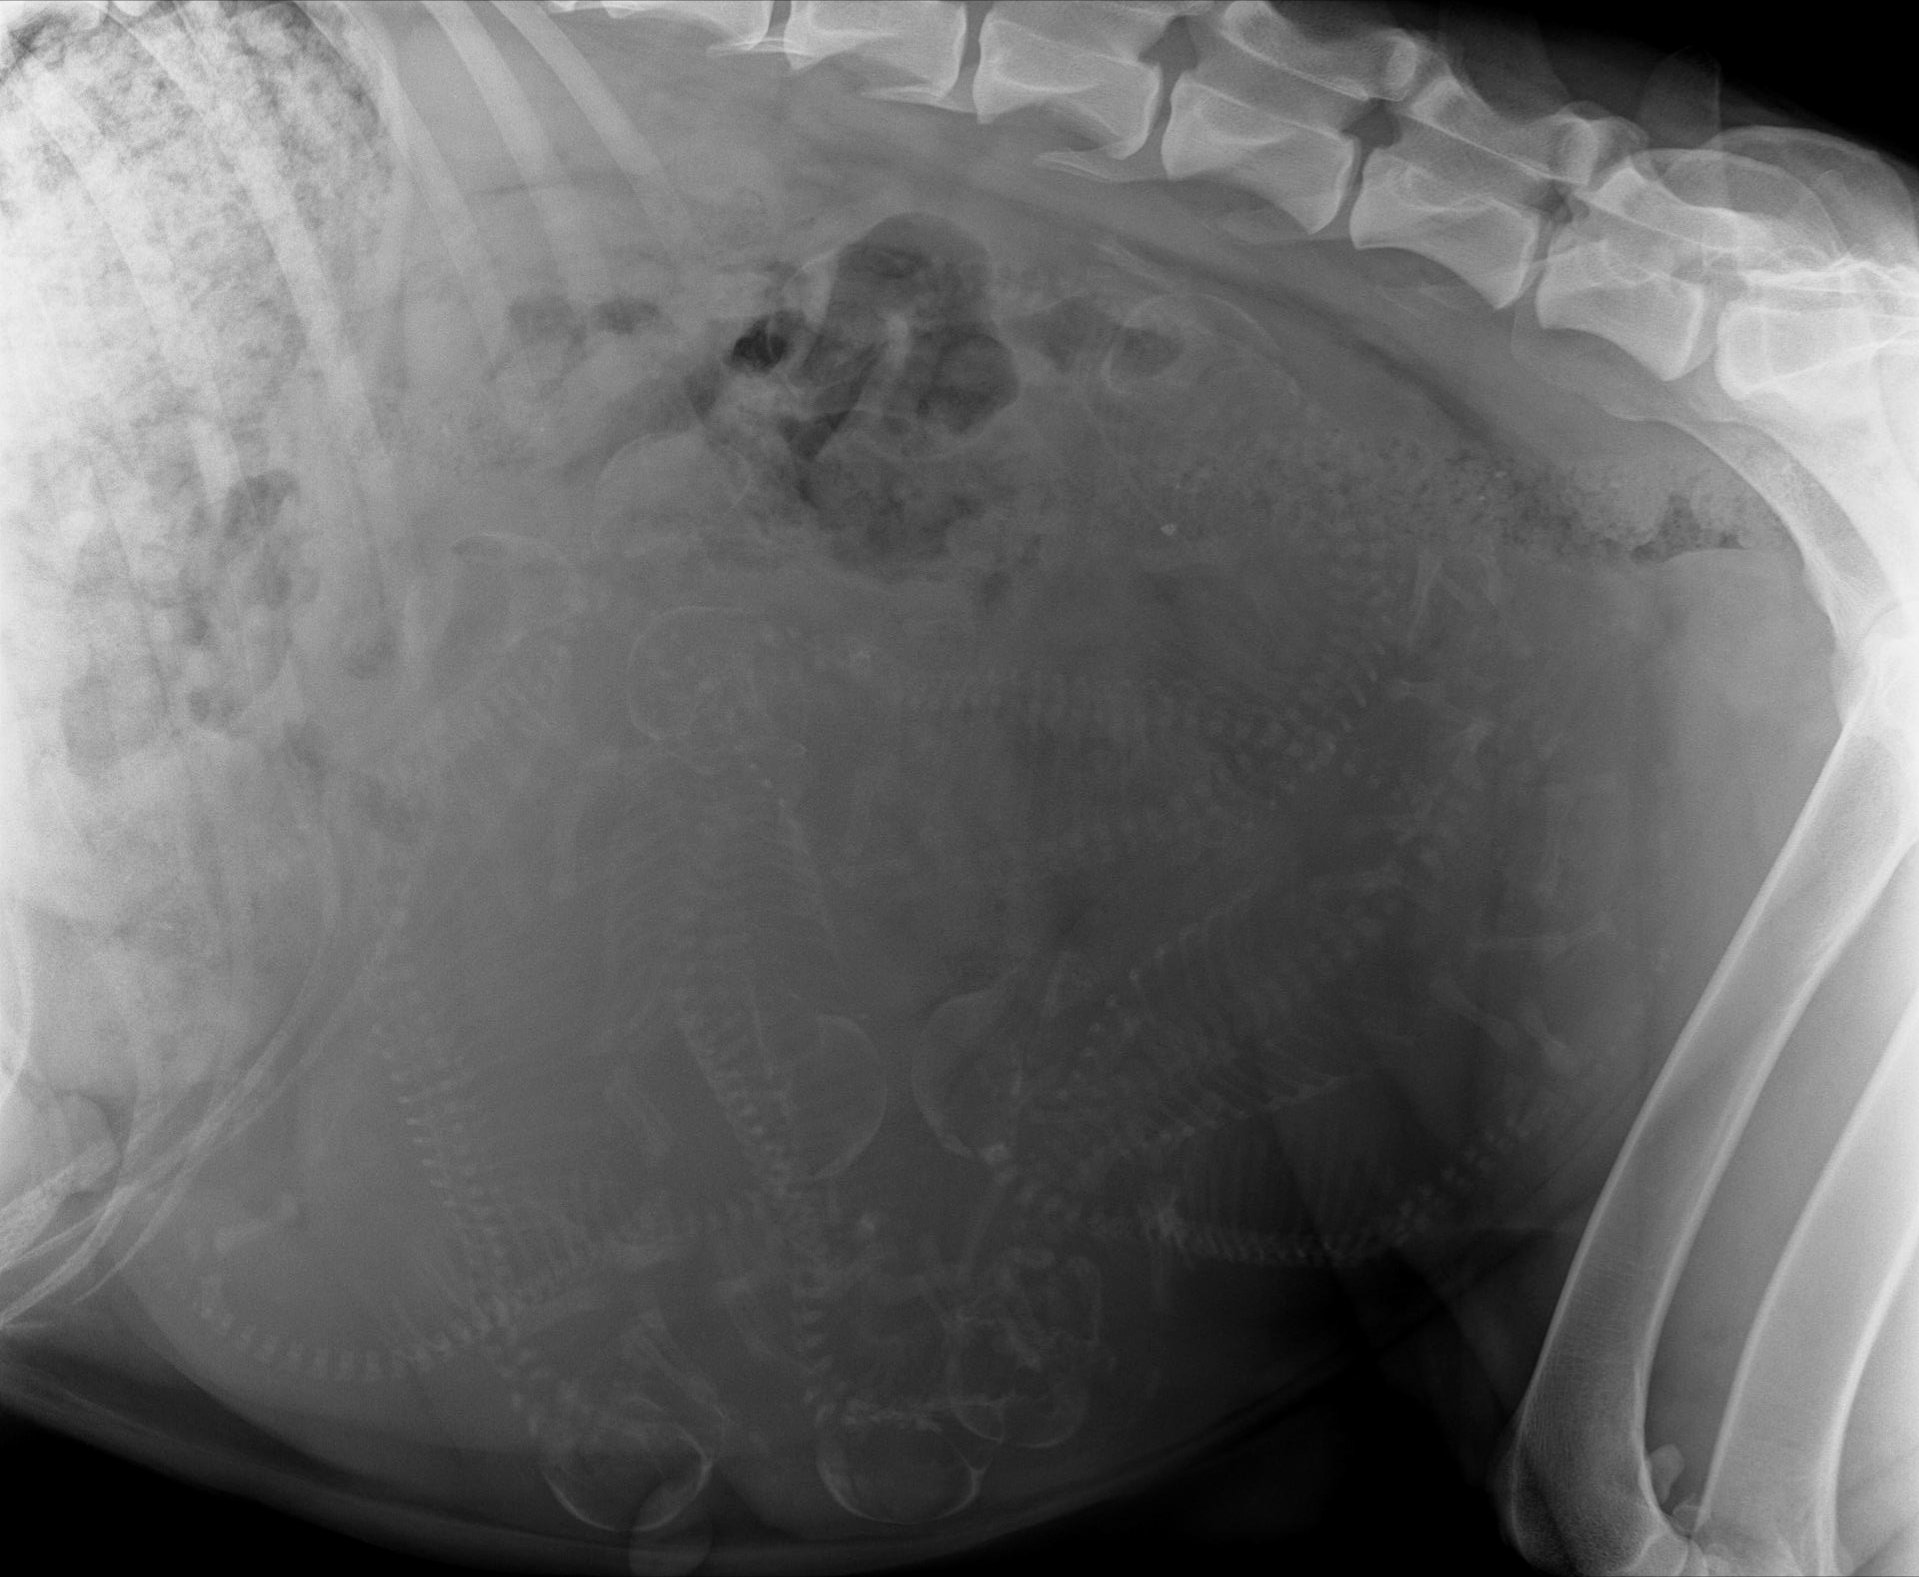

Radio de gestation de Bahia

Picoxia__2025-12-11_11-11__PERRET_Bahia_1.jpg